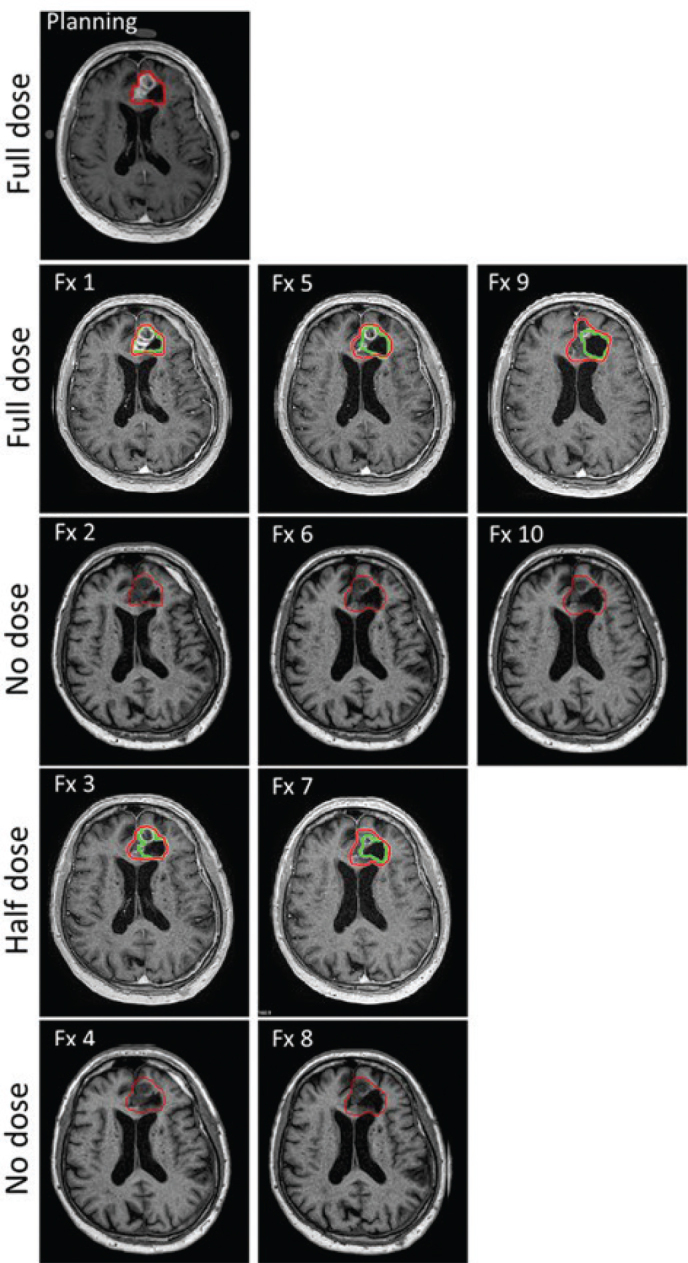

Background and purpose: Magnetic resonance imaging-guided radiotherapy (MRIgRT) enables precise tumour targeting through adaptive planning, which is particularly relevant for glioblastoma due to its dynamic morphology. Gadolinium-based contrast agents (GBCAs) enhance tumour visibility, but frequent use during MRIgRT raises safety concerns related to cumulative gadolinium exposure. This study investigated the feasibility of a reduced GBCA dose protocol for patients with glioblastoma undergoing MRIgRT, aiming to balance tumour conspicuity with minimisation of GBCA-related risks. Patient/material and methods: Nine patients with glioblastoma received hypo-fractionated MRI-Linac radiotherapy (10 × 3.4 Gy) with MRI performed with either full-dose, half-dose or no GBCA enhancement. Online gross tumour volume (GTV) delineation was performed by radiation oncologists, while offline GTV delineation was independently conducted by an expert neuroradiologist on GBCA-enhanced scans. Objective assessment using automatic thresholding and a structured Likert-scale evaluation were also performed.

Results: During online adaptation, GTV volumes generally remained stable or increased, whereas offline expert assessments revealed a general volume reduction and systematic volume underestimation with half-dose scans (~18%). Relative delineation volume discrepancies were most pronounced in small tumours. Structured radiologist feedback reported lower confidence, tumour conspicuity and image quality in half-dose scans, particularly for small lesions. Otsu's thresholding revealed reduced edge definition with decreasing contrast dose. No signs of GBCA retention were observed between fractions.

Interpretation: Reduced-dose GBCA-protocols are feasible. Full-dose contrast is recommended at key fractions (e.g. baseline and mid-treatment) and for small tumours, with half-dose imaging reserved for selected intervals or larger tumours. This hybrid approach may balance safety and imaging precision in adaptive MRIgRT.